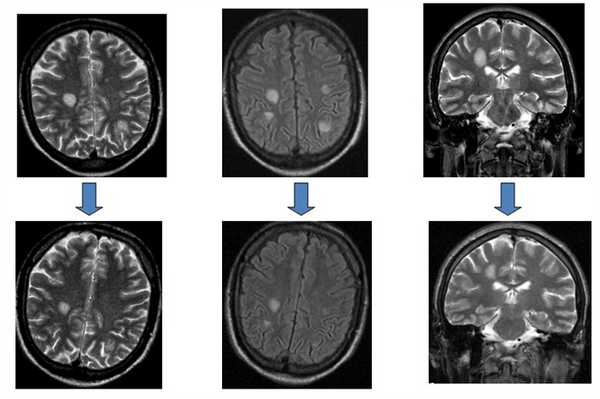

МРТ головного мозга. Т2-взвешенные аксиальные МРТ типа FLAIR. Динамика очагов за полгода.

Множественные асимметричные очаговые изменения глубинных отделов белого вещества с зубчатыми контурами, преимущественно локализующиеся в теменно-затылочной области, не оказывающие масс-эффекта и не накапливающие контраст.

Поражения серого вещества не типичны.![Поражение головного мозга при ВИЧ инфекции]()

Очагово-диффузные изменения белого вещества мозжечка, ствола мозга и больших полушарий (а,в)

Участки накопления контраста в отдельных очагах демиелинизации (б,г)Криптококковая инфекция